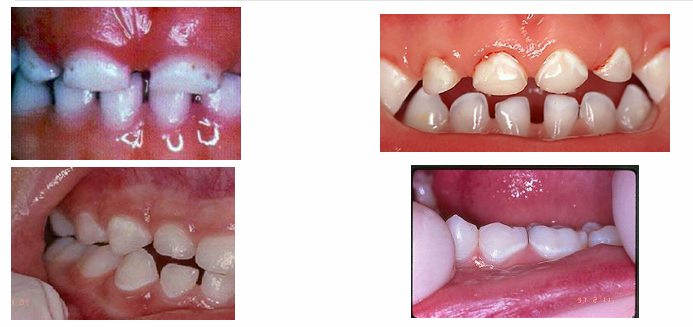

early signs of decay

-white spot lesions

-not as visible when dry → become chalky

later signs of decay

-enamel breakdown

advanced/severe decay

-decay that extends all the way to the gingiva anteriorly or very extensively occlusally in the posterior